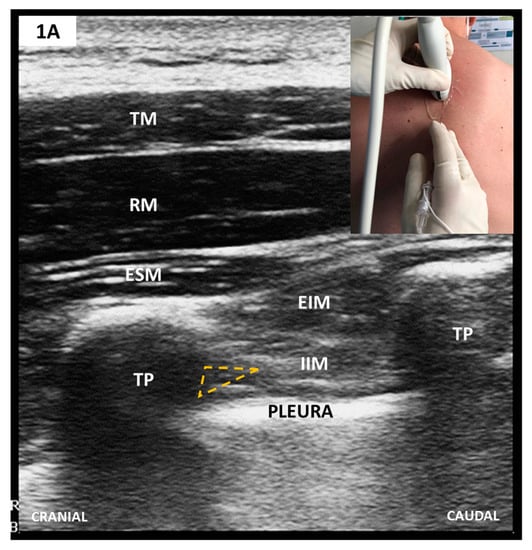

2.2. Paravertebral Blocks (PVB)

Sonoanatomy and Block Techniques (Figure 1)